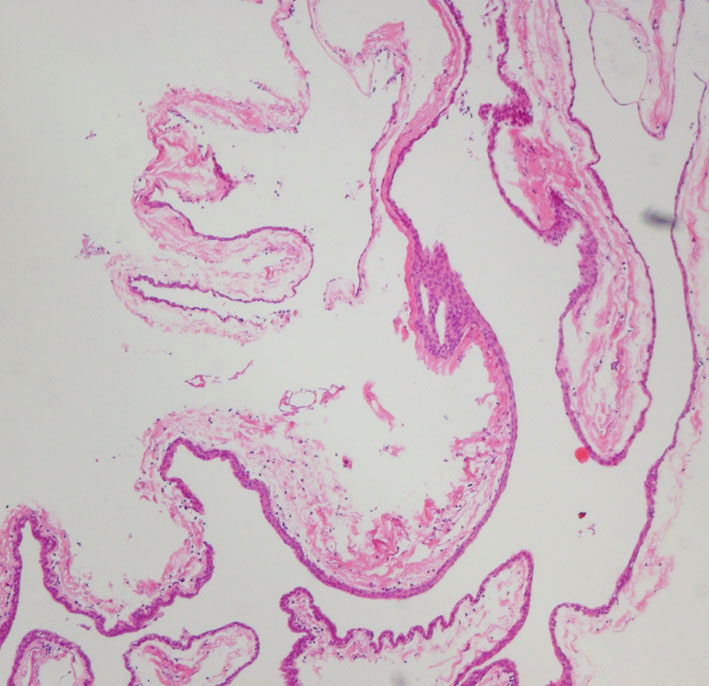

前頭側頭開頭 pterional approachで全摘出しました。発生母地は下垂体柄前面でしたが完全摘出しました。術後に下垂体機能は正常に保たれています。病理所見は一層の上皮細胞でのう胞壁が構成されることが特徴です。これをラトケのう胞と呼ぶかどうか議論のあるところで,おそらく正確には内胚葉のう胞 endodermal cystと診断します。